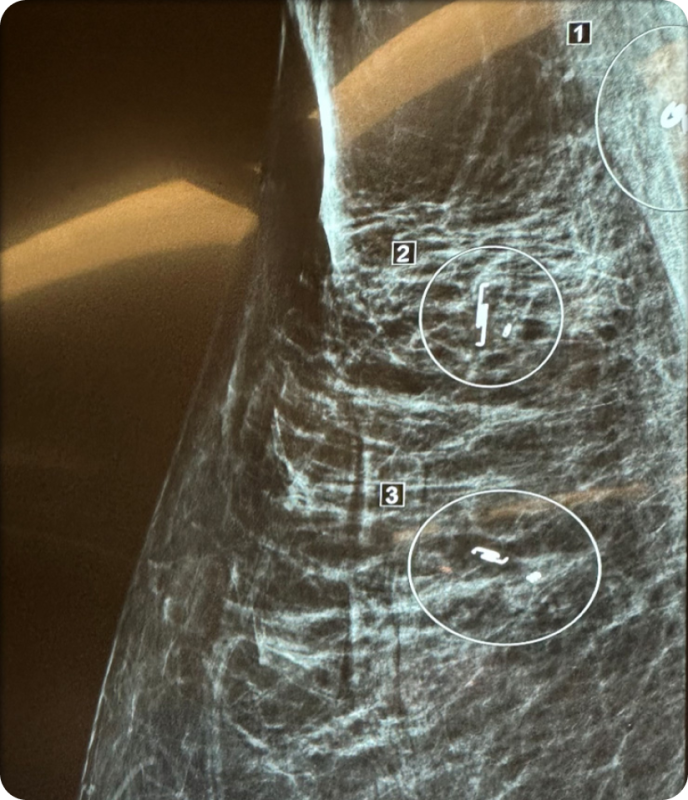

Breast-conserving surgery often requires precise localization of tumors that are difficult to detect. SCOUT MD provides a wire-free alternative by placing tiny reflectors before surgery, enabling surgeons to accurately locate tumors, map margins in real time, and preserve healthy tissue, reducing the need for additional procedures. Its four distinct reflector shapes allow for precise margin mapping and multiple lesion localization, offering greater flexibility and accuracy in complex cases.